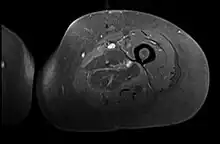

Axial fat suppressed T2 weighted MRI image showing hyperintense signal and enlargement of the left thigh adductor muscle group in diabetic myonecrosis.